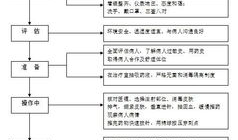

肌肉注射操作视频,步骤与技巧全解析

亲爱的读者们,你是否曾经好奇过,那些在医院里忙碌的医护人员是如何进行肌肉注射的?今天,就让我们一起揭开这个神秘的面纱,通过一段特...